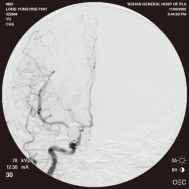

右侧颈内动脉后交通动脉瘤栓塞术前 左椎动脉造影 示左椎动脉夹层动脉瘤: 左椎动脉发出小脑后下动脉处呈囊性扩张,动脉瘤远端血管狭窄

弹簧圈栓塞后造影示左椎动脉夹层动脉瘤消失, 左椎动脉、 多发动脉瘤夹闭术前、术中

左侧小脑后下动脉循环通畅